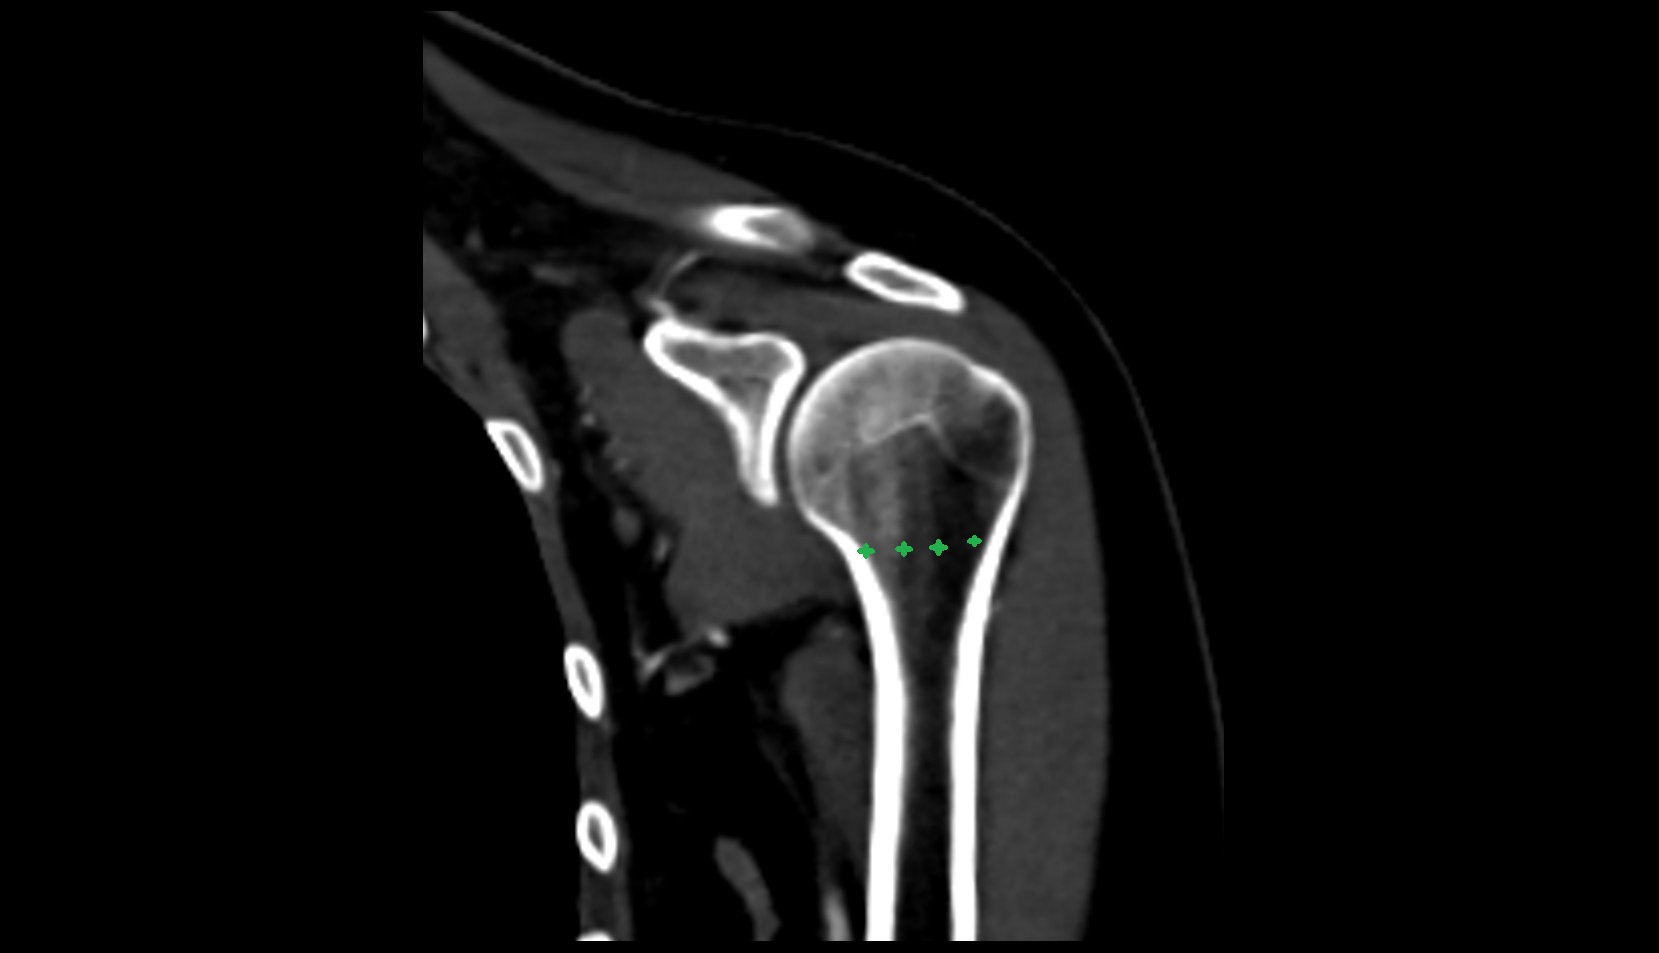

- Glenoid fossa

- Glenoid process of scapula

- Spine of scapula

- Acromion process of scapula

- Coracoid process of scapula

- Scapular body

- Humerus

- Head of humerus

- Shoulder joint (glenohumeral joint)